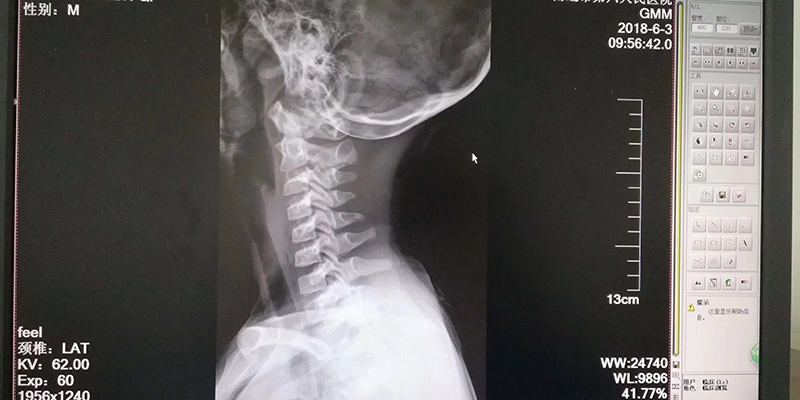

颈椎弧度变直、腰椎侧弯畸形、椎间盘膨凸等退行性改变,以前都是“成人病”,可现在却连孩童都患上了这样的病。学期期末将近,南通市第六人民医院中医科连续接诊多例颈腰椎疼痛的学生患者,最小的才9岁。虽然通过相关针灸、手法矫正、颈腰椎牵引、超短波静电治疗,配合颈腰椎固定,经过一个疗程一周治疗后,患者的疼痛普遍改善,但这样的案例向家长们敲响了警钟,如果发现孩子有颈腰椎疼痛不适,要及时就医。

六院中医科花佳佳主任介绍道,一些学生由于长时间伏案上课、学习、作业,不注意坐姿,腰部长期保持弯曲姿势,导致腰部脊椎向前弯曲,长此以往,颈腰椎就会慢慢发生病变。如果腰椎间盘长期受压,久拖不治,压迫到神经脊髓,就需要手术,否则,严重的可能造成截瘫。

还有一些小学生,甚至学龄前儿童,过度使用手机和平板电脑,一坐就是三四个小时甚至更久,长时间低头,致使颈椎、肩膀、胳膊、腰部酸胀疼痛。同时又不注意作息,造成反复疼痛,对青少年生长发育、学习、生活造成严重的影响。“低头看手机和平板电脑,颈椎所承受的重量是垂直时的3倍。”花佳佳说,当玩手机时,如果姿势不当,可能让颈椎承受多达27公斤的重量,相当于将6个西瓜一直挂在颈椎上。